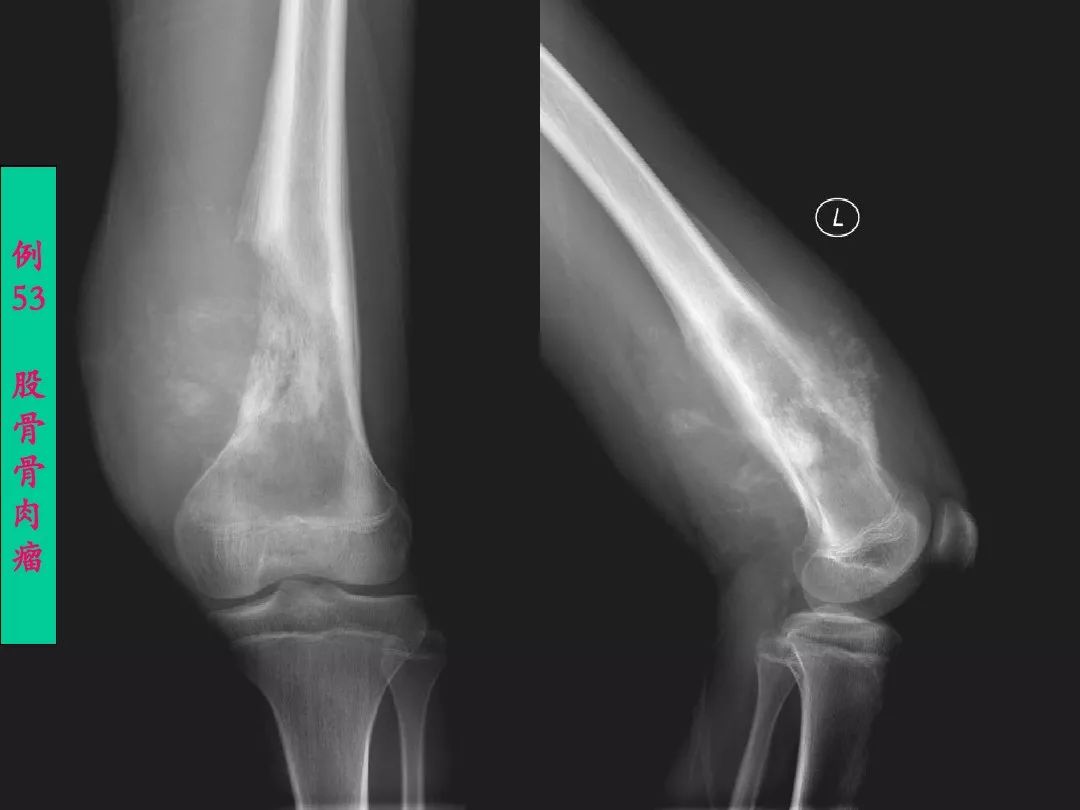

膝关节正常解剖及常见病变的影像表现